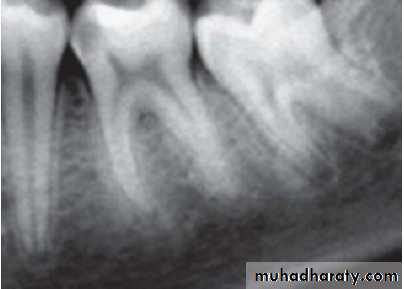

4. Radiographs

3. Radiographs: These show normal PDL and lamina dura.– Depth of caries or restoration may be evident.

Visual examination and history: Examination of involved tooth may reveal previous symptoms. On inspection, one may see deep cavity involving pulp or secondary caries under restorations.2. Radiographic findings:

– May show depth and extent of caries.– Periapical area shows normal appearance but a slight widening may be evident in advanced stages of pulpitis.